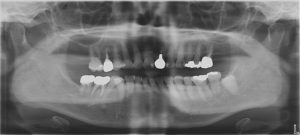

下の写真はインプラントを埋入する前のパノラマ写真です!写真は左右変転して見て下さい!

下の写真はインプラントを埋入する前のパノラマ写真です!写真は左右反転して見てください(^^)